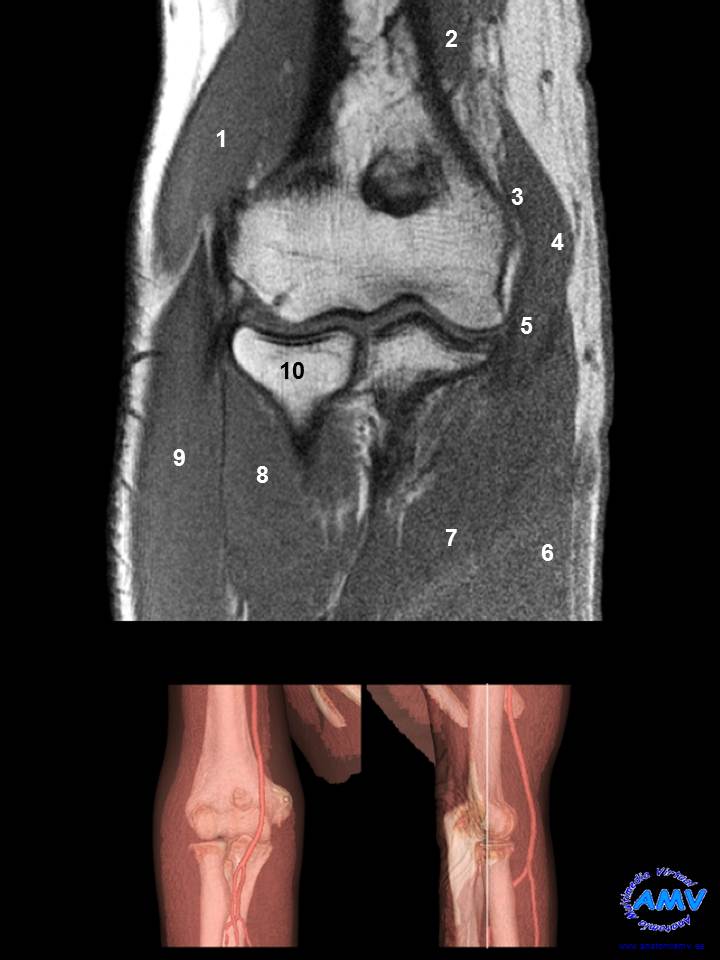

RMN Coronal de Codo

ms_rmn_06.jpgIndique que estructura se señala con el número correspondiente:

El nº 1 señala al músculo .

El nº 2 señala al músculo .

El nº 3 señala al músculo .

El nº 4 señala al músculo .

El nº 5 señala al músculo .

El nº 6 señala al músculo .

El nº 7 señala al músculo .

El nº 8 señala al músculo .

El nº 9 señala al músculo .

El nº 10 señala al hueso .